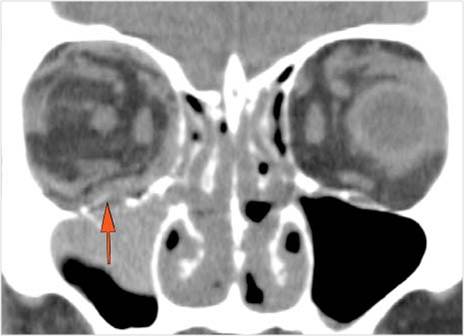

There is evidence of a subperiosteal hematoma along the medial or lateral wall, roof or floor of the orbit. [Yes/No]

There is evident subretinal, subchoroidal or intravitreous hemorrhage. [Yes/No]